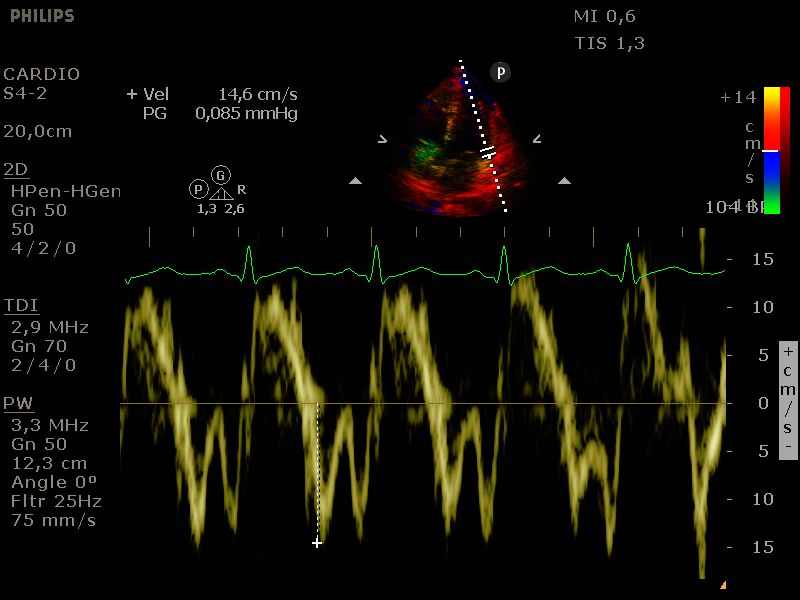

E-prime mitralisannulus

Bepaling laterale E' van de mitralisannulus door middel van tissue doppler